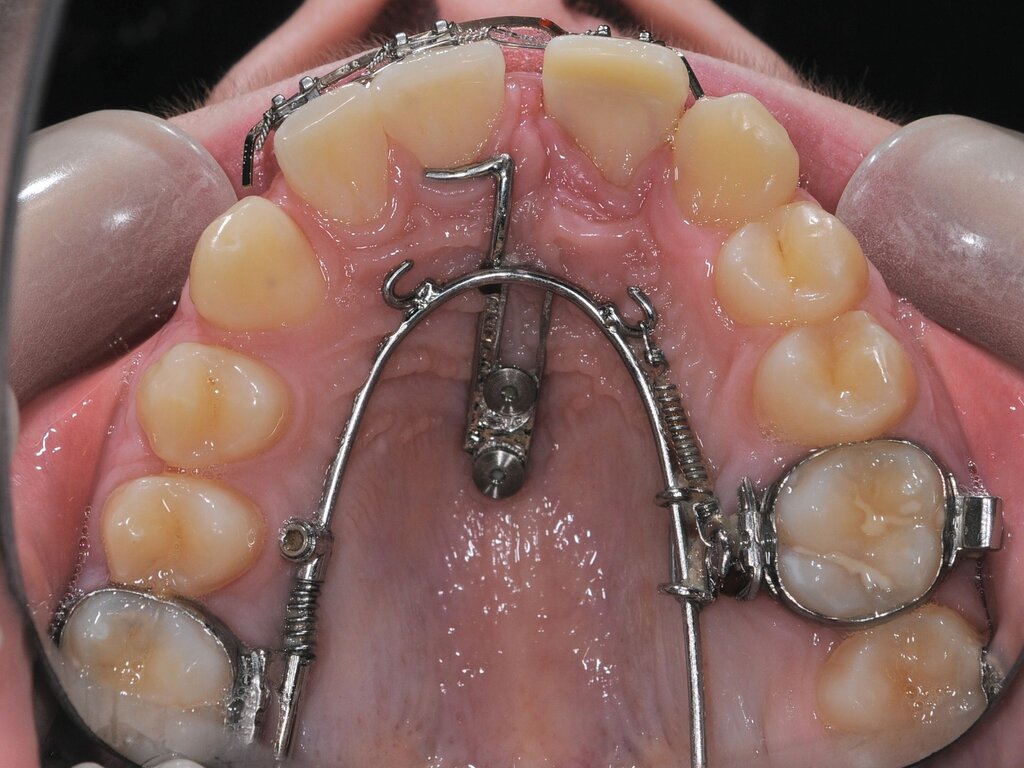

Durch den Einsatz skelettaler Verankerungshilfen ist es möglich, auch in komplexeren Situationen einen kieferorthopädischen Lückenschluss durchzuführen. Mit digitalen CAD/CAM-Herstellungsmethoden wie dem selektiven Laser-Melting-Verfahren können hochindividualisierte Apparaturen angefertigt werden, die verschiedene Behandlungsaufgaben gleichzeitig adressieren beziehungsweise mit deren Hilfe Kraftvektoren präzise geplant und appliziert werden können.

Zu den weiteren Vorteilen gehören die geringeren Nebenwirkungen auf die Nachbarzähne, die bessere Planbarkeit bei Set-up-basierten Apparaturen, die gute Pflegbarkeit, die einfache Handhabung, die Verkürzung der gesamten Behandlungszeit durch reduzierte Multibracket-Phasen sowie die geringere Beeinträchtigung der orofazialen Ästhetik (Abbildung 5).